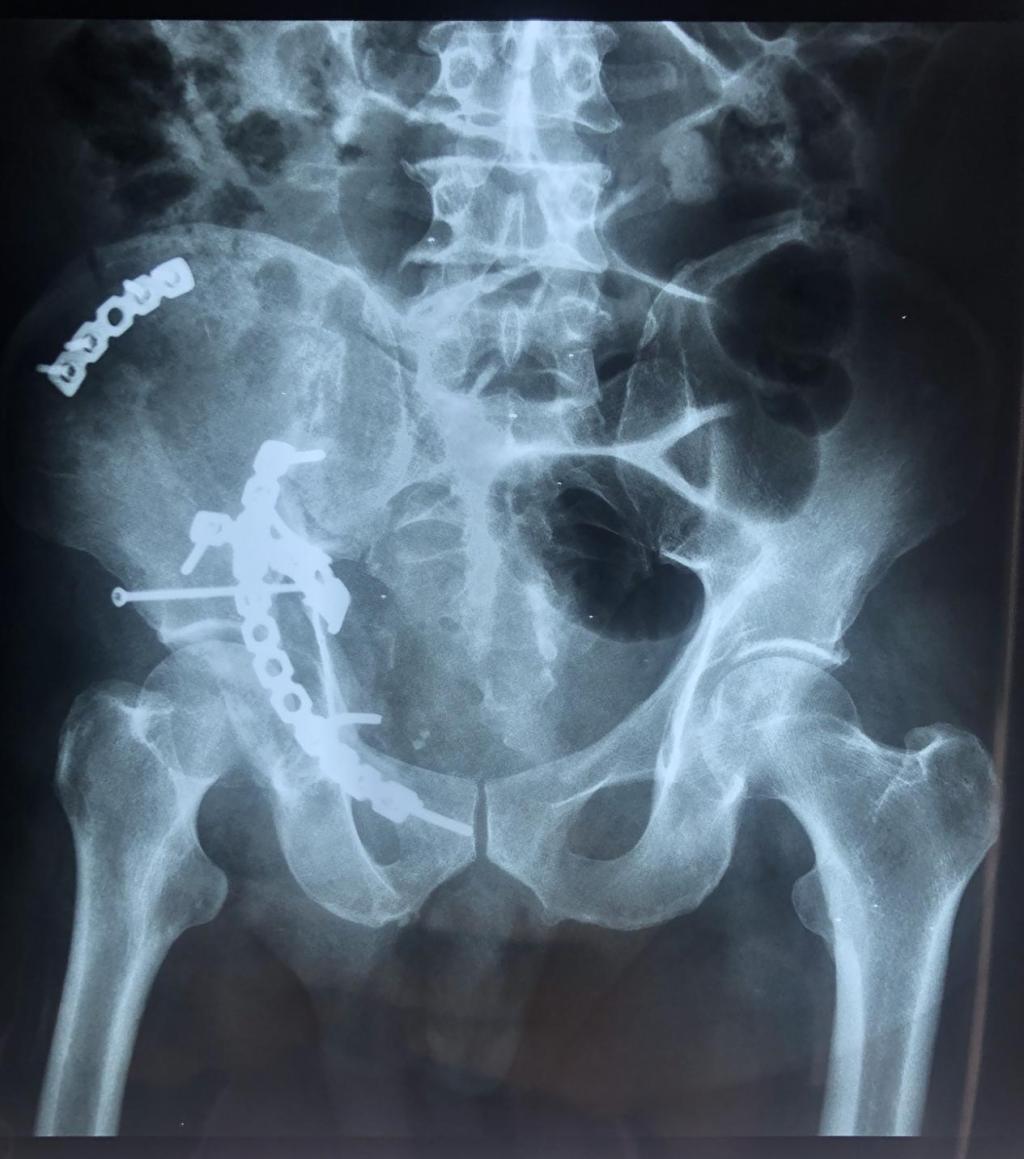

患者车祸致伤入院后,李玉民主任医师组织科内多次讨论认为,该患者为高能量损伤致复杂髋臼骨折,Letournel-Judet分型为高位前柱伴后半横骨折,股骨头中心脱位致臼顶、四方体粉碎性骨折,后柱横断向后方移位,前柱高位骨折伴旋转移位,头臼不匹配,臼内台阶明显,髋关节失去正常形态,失去明显的解剖标志,严重功能受限。须尽早积极手术治疗,否则后期出现畸形愈合关节功能丧失,股骨头坏死,致残率增高失去劳动能力。

经严谨的术前规划及方案设计,11月7号由郭宏军主任医师医疗组给予单一前方经腹直肌旁入路手术内固定。术后患者右髋关节功能恢复良好,自行翻身,半靠体位均不受限。

该患者伤后三周手术,骨折端已明显骨痂包绕,显露不易,术后给予高位前柱截骨使得髋臼骨折易于解剖复位固定,恢复了髋臼关节面光滑连续完整,头臼匹配良好,预防了股骨头后期坏死,使患者能够早期功能锻炼,最大程度减少了致残率,早日恢复劳动力。